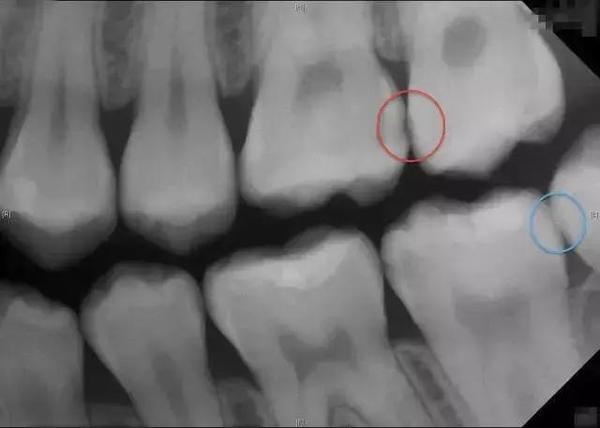

根尖片:紅圈處的牙縫有初期蛀牙,牙冠有黑色陰影;藍圈處的牙縫沒蛀牙,可看到完整牙冠。